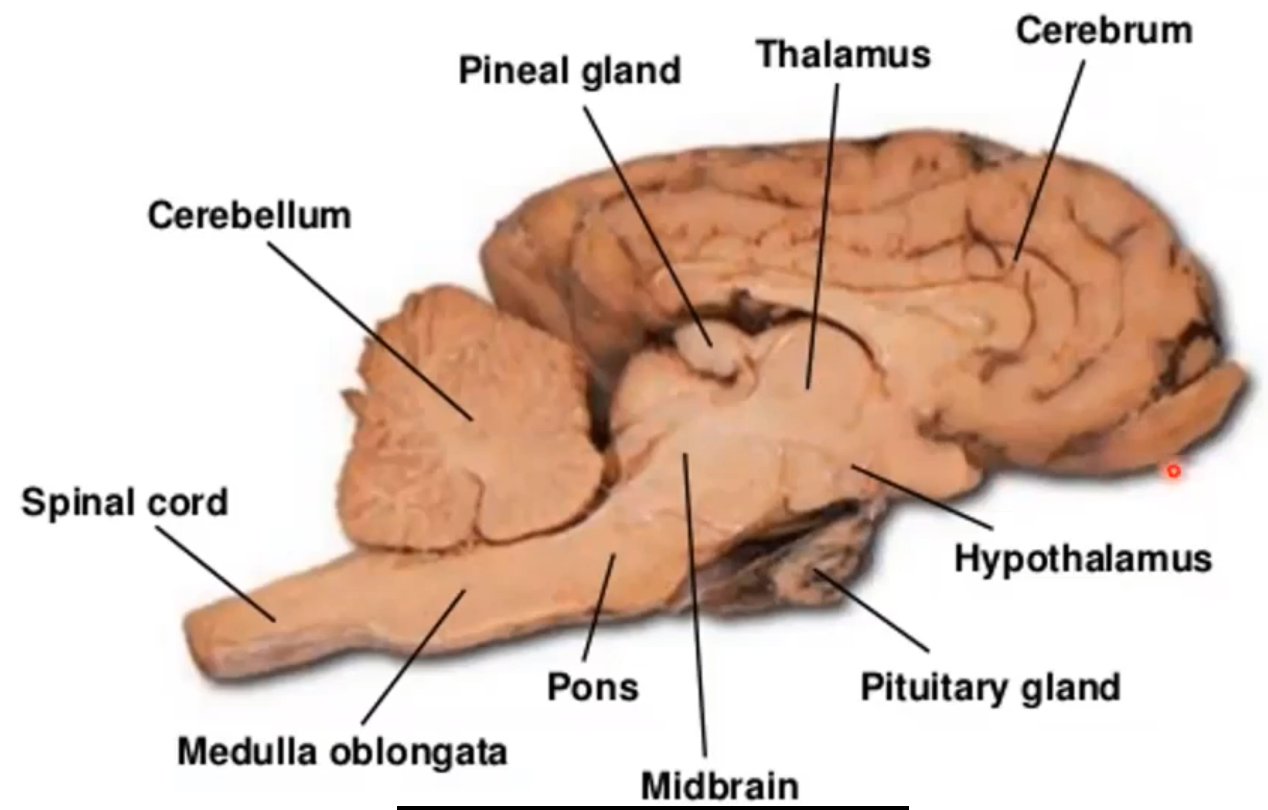

Name of Ridges Depression

Cerebral cortex

Coordinate language, thought, decision

“Grey matter”

Ridges: Gyrus

Depression: Sulcus

Name

Corpus callosum

Lobe Name

Frontal Lobe

Lobe

Temporal Lobe

Name

Thalamus

Lobe

Occipital Lobe

Lobe name

Parietal lobe

Name

Hypothalamus

What + (Two halves)

Midbrain

Superior Colliculi (Function not needed to remember)

Inferior Colliculi

Name+ inside (not asking for lobe name)

Cerebellum

Has arbor vitae inside, sensory motor information

Name

Pons

What is the nerve on the red dot

Olfactory bulb

Name

Medulla Oblangata

What nerve

Optic Nerve

Optic Chiasma

Right side is processed by left cerebral hemisphere

Name

Pineal Body

What produces releasing/inhibiting hormones

hypothalamus

Name + Function of two halves

Pituitary